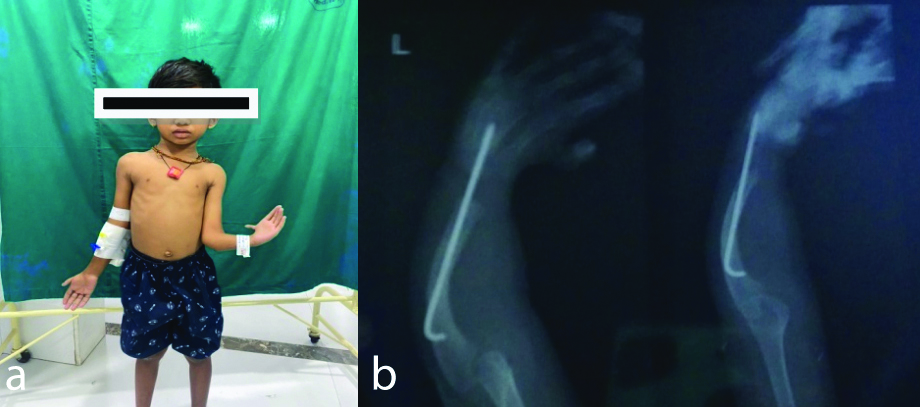

Radiological investigations showed a normal chest X-ray. The hand X-ray revealed a rod insertion for a radial abnormality and a K-wire for a finger procedure performed when the child was two years old [Table/Fig-1]. Ultrasonography of the abdomen and pelvis showed bilateral increased renal cortical echogenicity and mild ascites.

a) Classic deformity in the left upper forearm and hand. b) X-ray for the corrected deformity.